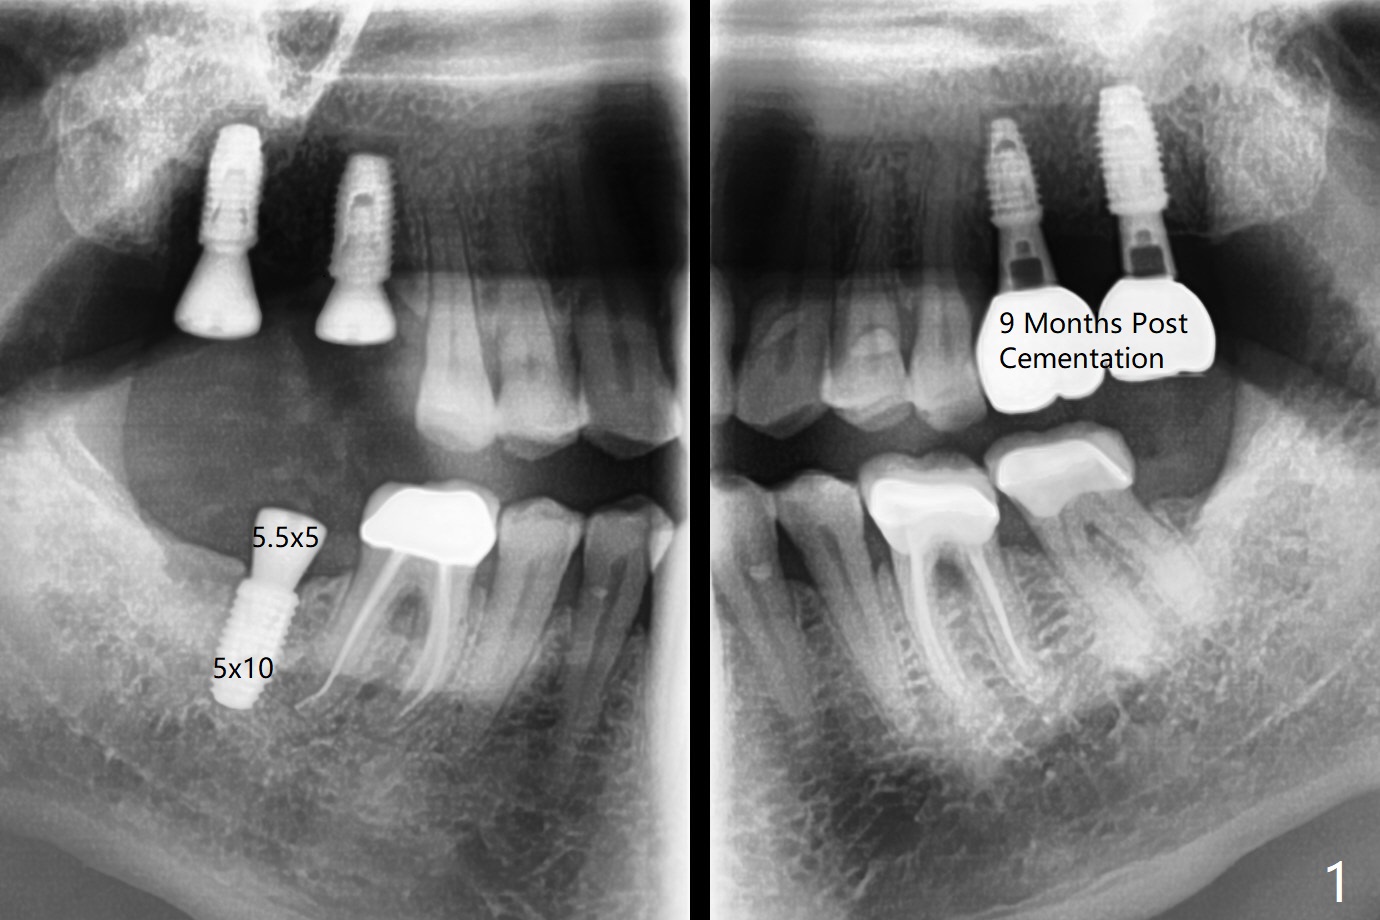

Incision is made at #2 and 3 because of bone graft palatal to #2 after implantation and 6-month-old guides (coronavirus pandemic). The implant at #3 is first placed with precision; there is no hesitation with that at #2. The palatal bone defect is confirmed. With autogenous bone placed around the implant/abutments covered by pieces of collagen membrane, the wound is closed with 4/0 Chromic gut suture. Since the keratinized tissue is wide at #31, osteotomy starts with a tissue punch. The implant placement level is noted accurate clinically and radiographically (Fig.1,2). The 3 implants have the same size (5x10 mm). All of the sites use 6.0 mm bone profile drill before healing abutment insertion. The surgery turns out to be smooth and streamlined. Abutments are placed 5 months postop (Fig.3,4). The upper crowns are redo twice because of light occlusion and proximal contact and finally are cemented 9 months postop with torque at 20 Ncm.